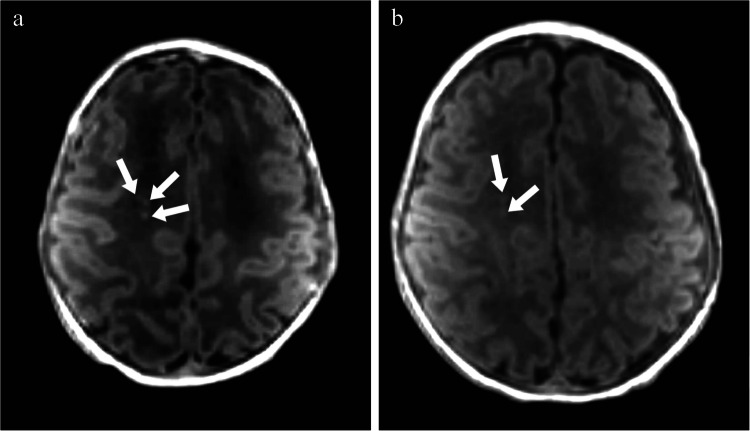

Abstract Image